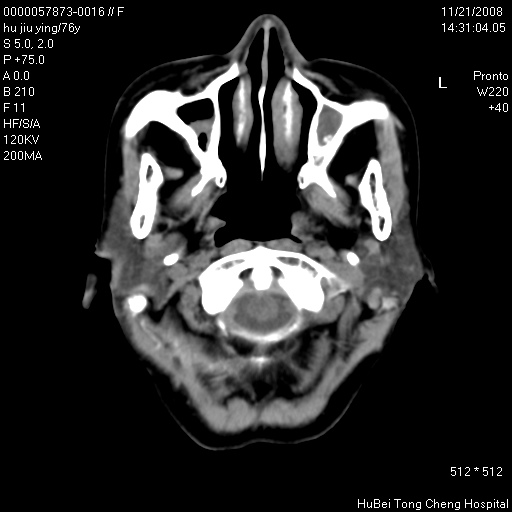

患者 女,76岁。左颈部包块20余天。pe:左侧扁桃体ⅲ度肿大,表面不平,有新生血管,右咽柱红肿,无溃疡。左颈上部包块约3cm×4cm大小,质中等,压痛,边界不清,不能移动。

临床诊断:左侧扁桃体肿瘤?

咽部及颈部ct轴位平扫(层厚、层距均为5mm),图像如下:

左侧咽旁软组织密度肿块影,形态不规则,与周围结构分界欠清,性质待定,建议增强;另双侧上颌窦炎.

支持:1)左侧扁桃体肿瘤;

2)双侧上颌窦炎症。